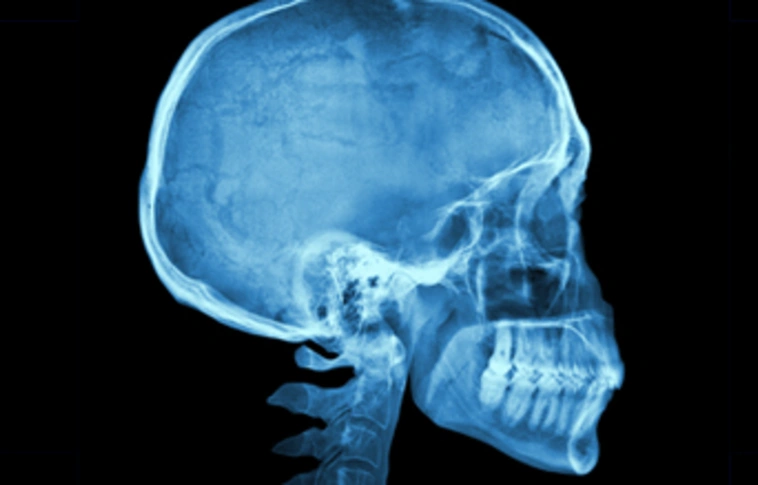

Koponyasérültek diagnosztikájához szükséges új eszköz kifejlesztésében vesznek részt magyar kutatók

Enyhe és közepesen súlyos koponyasérültek agykárosodása súlyosságának megállapításához használható, új - biomarkerek vizsgálatán alapuló - diagnosztikai eszköz kifejlesztéséhez szükséges kutatásban vesznek részt magyar szakemberek.